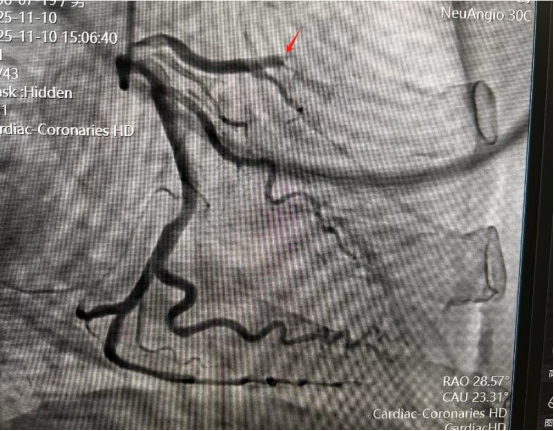

患者为一名67岁男性,因反复胸闷6个多月,胸痛伴心累气紧近一周,遂前来我院就诊。经过接诊医生初步诊断为冠状动脉粥样硬化性心脏病,在完善各项相关检查后进行了冠状动脉造影,造影发现该患者左侧冠状动脉前降支中段血管存在闭塞,传统的介入手术中,医生主要依赖冠状动脉造影来引导操作。然而,造影提供的仅是二维的血管“影子”,对于血管壁的内部结构、斑块的性质、闭塞段的真实长度及原因,如同“雾里看花”,难以精确判断。这使得手术具有一定的“不确定性”,尤其在处理完全性闭塞等复杂病变时,犹如在黑暗中摸索,导丝能否成功通过、支架尺寸选择是否最佳、贴壁是否完美都面临着巨大挑战。

术前造影